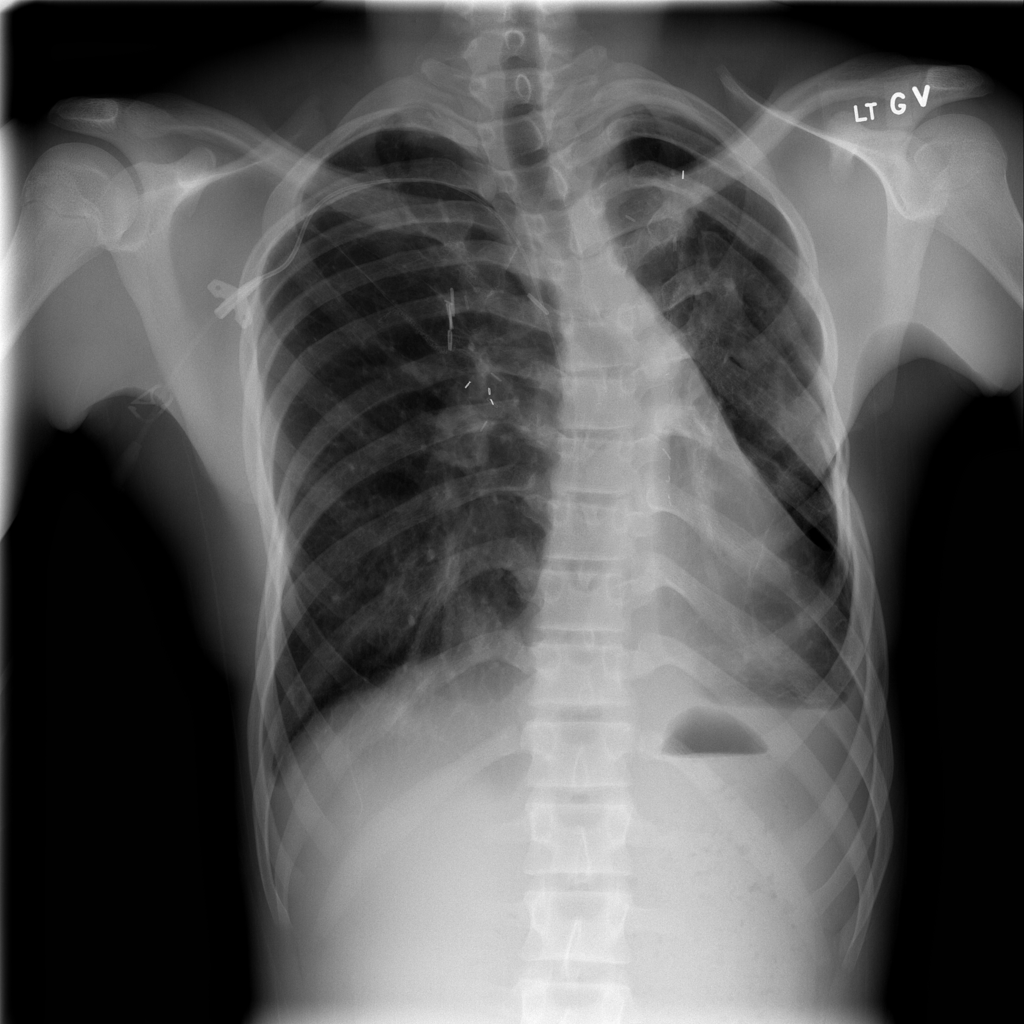

PAT-50E5 · IMG-008Mass

PAT-50E5 · IMG-008

PA